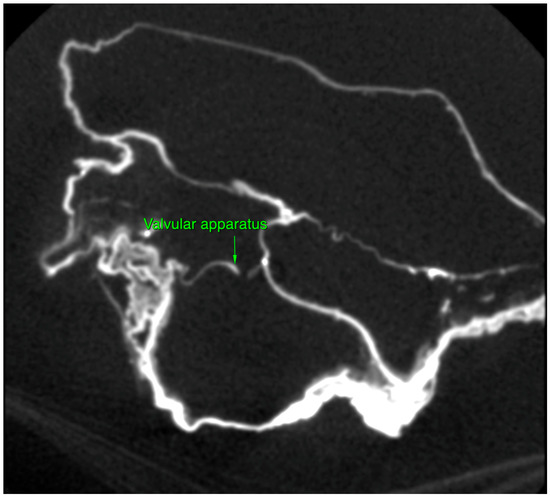

2.2. Micro-CT Scan

4.2. Micro-CT Scan